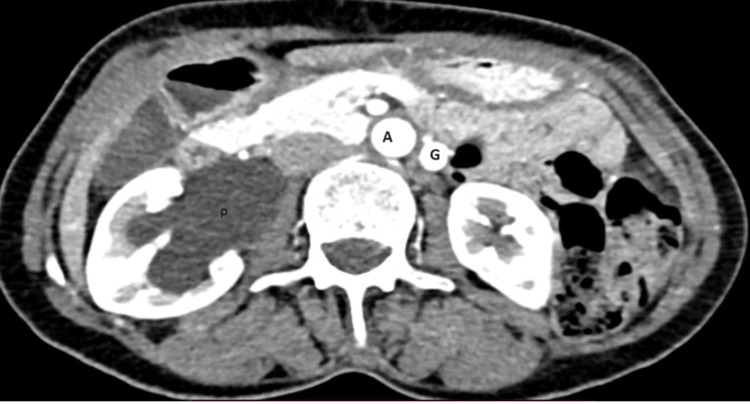

我们报告了一例罕见的左侧胡桃钳综合征和右侧输尿管盆腔交界处梗阻(UPJO)并发症,该患者为成年女性,在出现间歇性双侧侧腹疼痛后经 CT 尿路造影确诊。为此,我们为她实施了安德森-海因斯肾盂成形术(Anderson-Hynes pyeloplasty)以治疗右输尿管盆腔梗阻,最初是在腹腔镜下进行的,但由于支架植入困难而改为开腹手术。她术后恢复顺利,术后第三天就出院了。胡桃钳综合征的症状对患者来说并不严重,因此我们计划对她进行保守治疗。

We report rare case of concomitant left nutcracker syndrome and right ureteropelvic junction obstruction (UPJO) on adult female patient diagnosed by CT urogram after she presented with intermittent bilateral flank pain. For this we did Anderson-Hynes pyeloplasty for right ureteropelvic obstruction, it was laparoscopic initially but due to difficulty of stenting it is changed to open. She had smooth post-op course then discharged on 3rd post-op day. Symptoms of nutcracker syndrome are not that much bothersome for the patient so we planned to follow her conservatively.